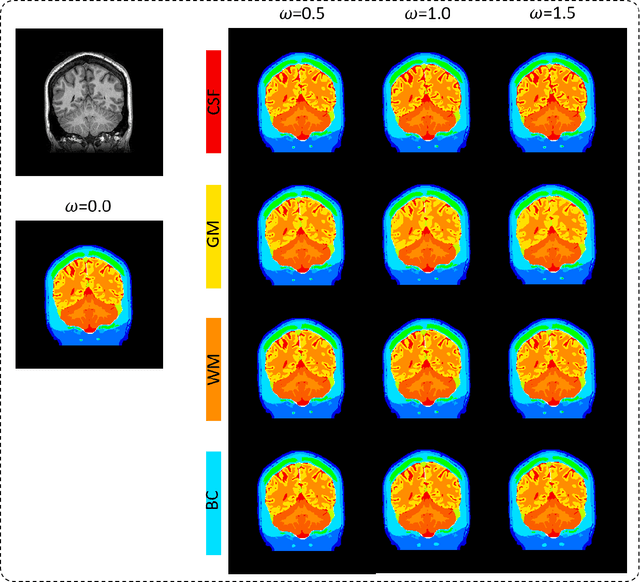

In several diagnosis and therapy procedures based on electrostimulation effect, the internal physical quantity related to the stimulation is the induced electric field. To estimate the induced electric field in an individual human model, the segmentation of anatomical imaging, such as (magnetic resonance image (MRI) scans, of the corresponding body parts into tissues is required. Then, electrical properties associated with different annotated tissues are assigned to the digital model to generate a volume conductor. An open question is how segmentation accuracy of different tissues would influence the distribution of the induced electric field. In this study, we applied parametric segmentation of different tissues to exploit the segmentation of available MRI to generate different quality of head models using deep learning neural network architecture, named ForkNet. Then, the induced electric field are compared to assess the effect of model segmentation variations. Computational results indicate that the influence of segmentation error is tissue-dependent. In brain, sensitivity to segmentation accuracy is relatively high in cerebrospinal fluid (CSF), moderate in gray matter (GM) and low in white matter for transcranial magnetic stimulation (TMS) and transcranial electrical stimulation (tES). A CSF segmentation accuracy reduction of 10% in terms of Dice coefficient (DC) lead to decrease up to 4% in normalized induced electric field in both applications. However, a GM segmentation accuracy reduction of 5.6% DC leads to increase of normalized induced electric field up to 6%. Opposite trend of electric field variation was found between CSF and GM for both TMS and tES. The finding obtained here would be useful to quantify potential uncertainty of computational results.